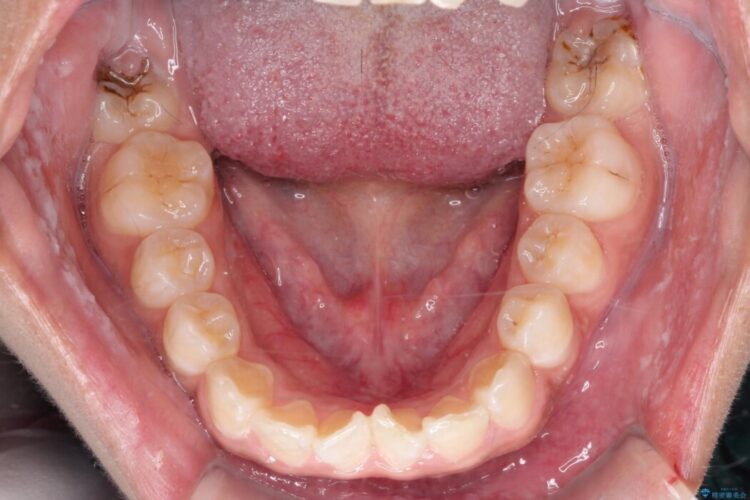

矯正検査の結果、歯列全体のスペースが不足しており、これが突出感の原因となっていました。

無理に歯を並べても口元の突出感は解消されないため、上下左右4番を抜歯しスペースを確保、目立ちにくい審美ワイヤー装置にて治療を行うこととしました。